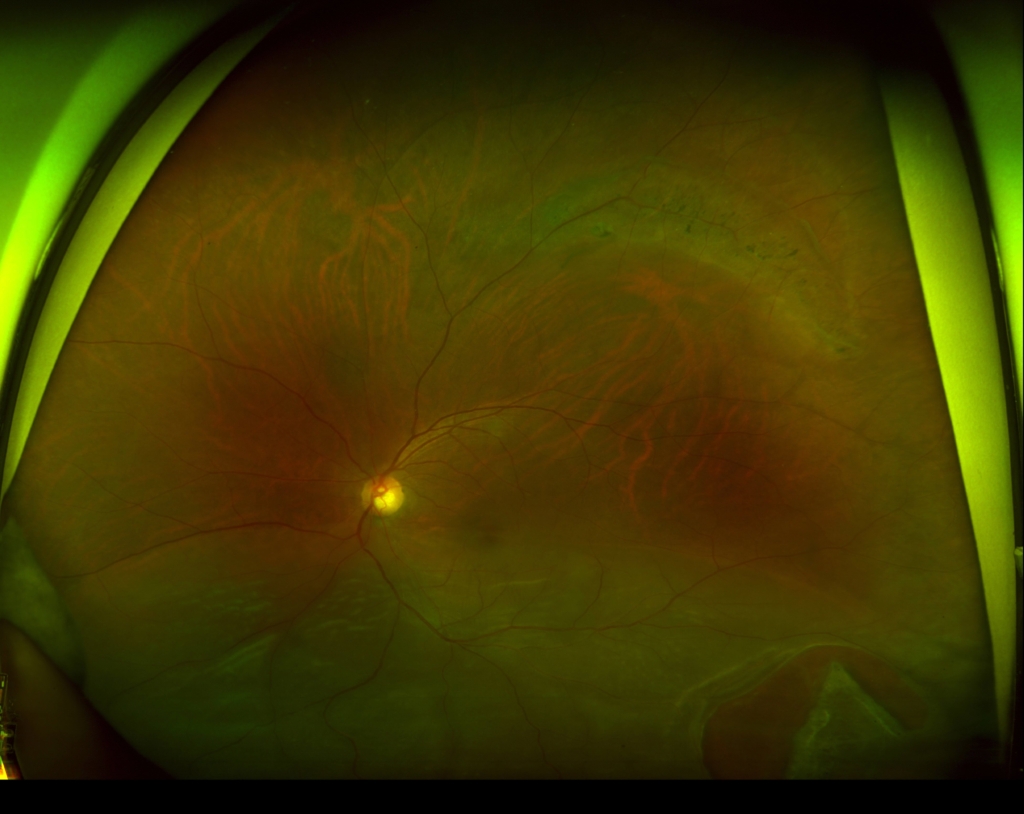

3時から8時に黄斑剥離を伴う胞状網膜剥離があり、4時に弁状裂孔がみられる。

12時から2時に格子状変性がみられる。